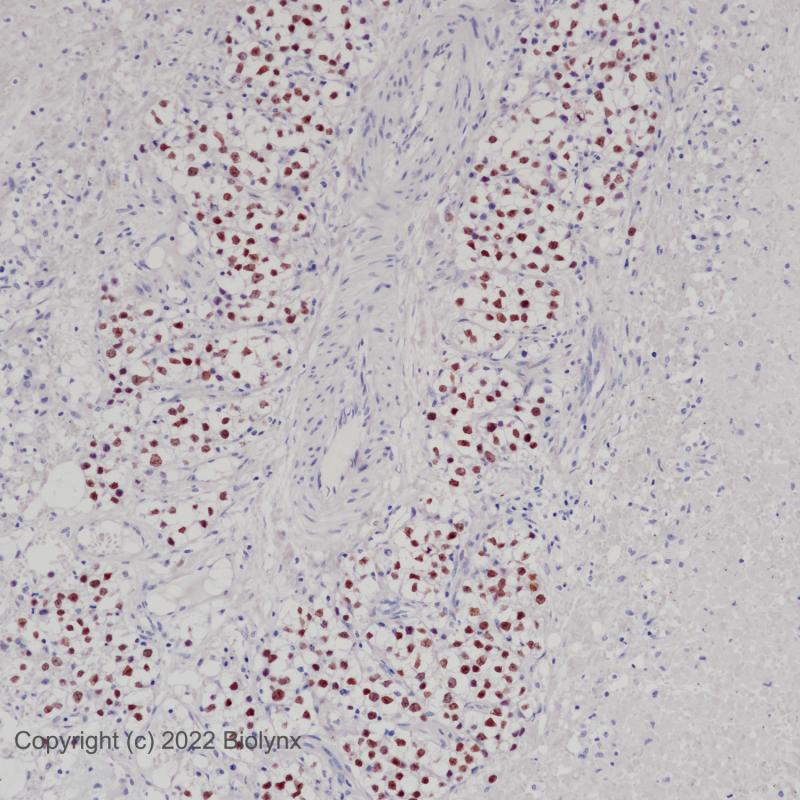

胚胎性癌SALL4(BP6204)染色

精原细胞瘤SALL4(BP6204)染色

SALL基因家族成员编码锌指转录因子在发育过程中高度表达。Sall-like蛋白4 (SALL4)是胚胎多能性的主要调节因子,并参与与干细胞活动相关的过程。正常睾丸的精原细胞中也有SALL4的表达。SALL4在生殖细胞中的表达使其成为生殖细胞肿瘤如精原细胞瘤、胚胎癌、卵黄囊瘤和畸胎瘤的有用标记物。

阳性对照

细胞核